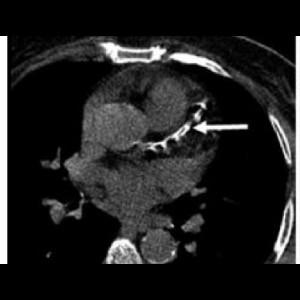

SYNTAX Score

SYNTAX Score in Patients with High Computed Tomography Coronary Calcium Score

SYNTAX Score

SYNTAX Score in Patients with High Computed Tomography Coronary Calcium Score